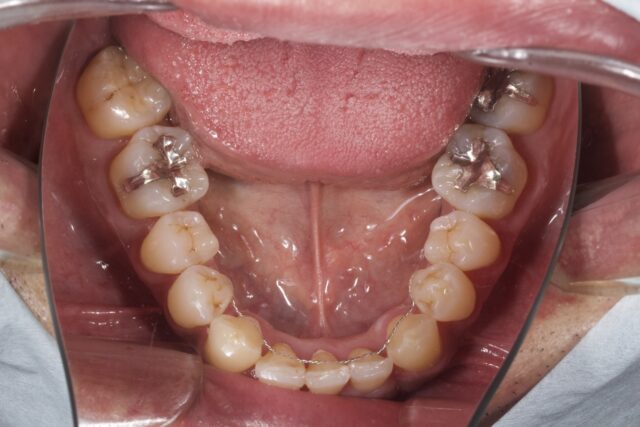

before

after